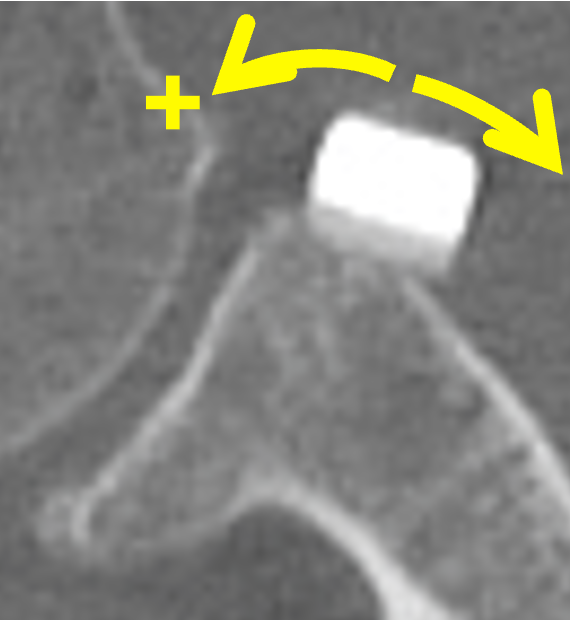

肩の受け皿(関節窩)に人工骨を移植し、骨の面積を広げることで、腕の骨が外に飛び出そうとするのを物理的にブロックします。

- 3D-CTによる科学的な評価 手術して終わりではなく、術後6ヶ月、1年と経過を精密な3D-CTで追跡。移植した人工骨がどのように自身の骨と馴染み、形態が安定していくかを詳細に検証しています(2024年 日本肩関節学会発表データより)。